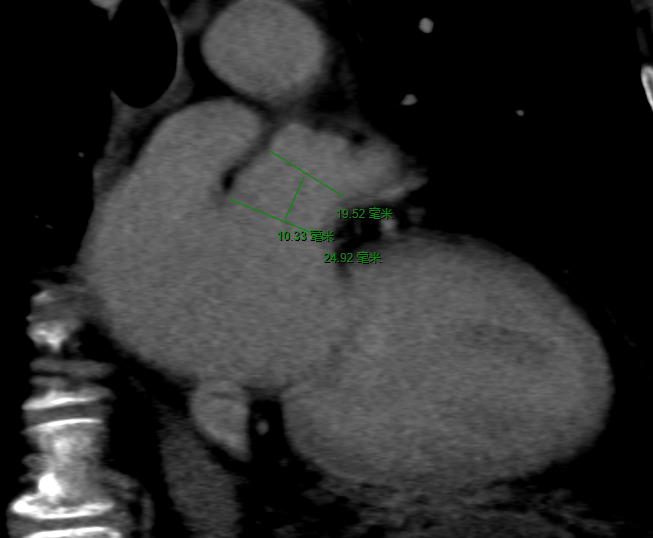

术前CT影像

术前CT结果显示,患者左心耳形态呈鸡翅形,开口呈椭圆形,开口大小约为25mm*20mm, 左心耳深径约20mm。为解决房颤引发脑卒中的后顾之忧,姜小飞教授团队为患者定制了射频消融+左心耳封堵术“一站式”手术解决方案,且由于患者心耳内腔较大,姜小飞教授选择LAmbre™左心耳封堵器进行封堵。